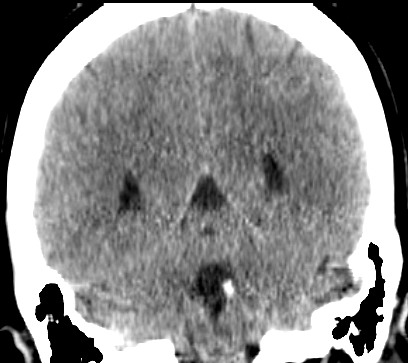

女,46岁,头晕1周。(第四脑室点状高密度灶,ct值约为65hu)。

四脑室脉络从钙化。

第四脑室脉络丛钙化。